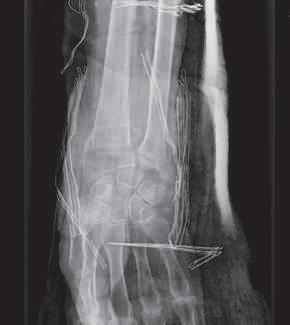

Lesões Ósseas

Palavras-chave: fraturas ósseas.

Keywords: bone fractures.

Introdução

O esqueleto do corpo humano é constituído por 206 ossos que são responsáveis pelas mais diversas funções, nomea damente: proteção dos órgãos internos, suporte mecânico, regulação da homeostasia mineral, funções hematopoiéti cas. Ao contrário dos outros tecidos no corpo humano que após lesão regeneram com tecido cicatricial, o tecido ósseo regenera com osso novo, indistinguível do osso original.

Devido à sua elevada área de exposição, o esqueleto apre senta, frequentemente, sinais de traumatismos, advindo daí a sua importância numa perspectiva médico-legal, quer em termos de patologia, quer de clínica forense. Após uma le são óssea, há a formação de um hematoma e uma resposta inflamatória que vai induzir a formação de osso novo por osteoblastos locais. Há a constituição de uma matriz co lagenosa e a diferenciação de células mesenquimatosas, com a formação de cartilagem. Os condrócitos proliferam, hipertrofiam e segregam fatores que vão induzir a ossifi cação da cartilagem, com a conversão de cartilagem em osso novo – ossificação endocondral. Este osso é remode lado pela ação combinada de osteoblastos e osteoclastos, dando origem a osso maduro de acordo com as linhas de stress/tensão (Clohisy et al., 2009). Dependendo do timing da lesão óssea, assim, poderemos ter lesões ante mortem, peri mortem e post mortem.

A presença de um calo ósseo, denotando assim um osso que teve tempo para maturar, aponta para uma lesão ante mortem. Já uma lesão que não apresenta sinais de conso lidação pode ter tido origem peri mortem ou post mortem A constituição do osso é alterada após a morte, com perda de água e da sua elasticidade, tornando assim o osso mais quebradiço, o que vai influenciar as características das lesões ósseas post mortem

Nas lesões peri mortem, encontra-se uma coloração mais uniforme e a presença de fraturas incompletas, em espiral e de tensão-compressão, frequentemente mais oblíquas. Nas lesões post mortem, em que o osso se encontra mais seco por desidratação, a coloração pode ser mais heterogénea

(por exposição ao meio envolvente), as superfícies de fratu ra vão apresentar-se mais regulares, com bordos retos, e as fraturas serão mais longitudinais e transversais irregulares (Cunha & Pinheiro, 2005/2006).

A forma e a aparência das lesões ósseas podem refletir não só a direção, a área, a velocidade, a massa e a forma do objeto produtor da lesão, mas também as próprias ca racterísticas inatas do tecido ósseo, como o seu conteú do mineral, as características físicas do osso em questão ou eventuais alterações patológicas do mesmo (Cunha & Pinheiro, 2005/2006). Sendo uma combinação de matéria orgânica e inorgânica, o tecido ósseo é capaz de sofrer de formação elástica e plástica antes da falência. Mas uma vez iniciada a fratura, esta propagar-se-á através do osso até que a energia seja dissipada.

Existem três tipos principais de lesões: cortantes, contun dentes e perfurantes. Quando há uma combinação destas, podemos ter lesões mistas, como as perfuro-contundentes provocadas por projéteis de armas de fogo. Por regra, os diferentes tipos de lesões apresentam características típi cas dos instrumentos responsáveis pelas mesmas, apesar de o mesmo instrumento poder ser responsável por diferen tes tipos de lesões e a mesma lesão poder ser provocada por instrumentos diferentes.

36.1

Lesões cortantes e corto-contundentes

As lesões provocadas por instrumentos cortantes vão de pender das características da sua lâmina, o que pode per mitir identificar o instrumento responsável pelas mesmas. É possível a análise da impressão provocada no osso – dos entalhes ósseos e dos seus bordos, paredes e pavimen tos – e identificar padrões nas estrias que permitam dis tinguir o tipo de instrumento. A análise das estrias através da microscopia eletrónica permite identificar imperfeições específicas das lâminas, o que pode levar à identificação do instrumento específico responsável por uma determi nada lesão. A partir da análise das lesões, pode ser ainda

© PACTOR 473

36

possível identificar a direção do movimento e os padrões de corte (Bartelink et al., 2001; Ciallella et al., 2002; Saville et al., 2007; Symes, 1992; Symes et al., 2001).

Assim, podemos encontrar lesões produzidas por instru mentos de gume liso, serrilhado ou complexo, simples ou duplo. Quando além da ação do gume o instrumento apre senta um peso elevado, vamos ter lesões de características mistas (corto-contundentes), como acontece com lesões

provocadas por machados, espadas ou catanas (Figura 36.1), que atuam pela ação do peso e do gume cortante (Humphrey & Hutchinson, 2001; Lewis, 2008).

As lesões ósseas do tipo cortante ou corto-contundente ocorrem em grande número no contexto de acidentes de trabalho com trauma dos membros superiores, nomeada mente das mãos (Figura 36.2).

Fig. 36.1 Lesão por catana

Fig. 36.2 Lesão por serra